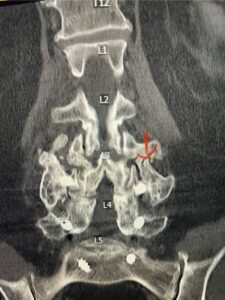

The patient had failed all means of conservative management including Physical Therapy and epidurals. He had an extensive medical history including stroke, cardiac stents, diabetes on insulin, hypertension, hypercholesterolemia, and kidney disease. Since he had a prior fusion with instrumentation for L4-S1, it was interesting that the patient had not developed significant next segment stenosis at L3-4. However, CT analysis (Fig. 2) demonstrated a partial fusion that extended from L3 to L4 which prevented abnormal motion.

Fig 2: Coronal lumbar CT demonstrating L4-S1 fusion with instrumentation with some incomplete bony fusion to the L3-4 segment (red arrow)